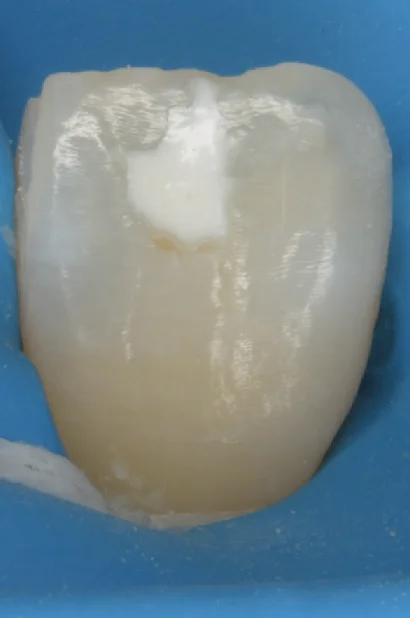

ICON治療(低侵襲ホワイトスポット改善治療)を始めました。

こんにちは。 先日・・・といっても割と前なんですけども、低侵襲レジンを用いたホワイトスポットの改善方法というセミナーを受講し、ICON治療という存在を知ることが出来ました。 そもそもホワイトスポットとは何かというと、 こんな感じで、歯の表面…

ICON治療にてホワイトスポットを改善。

こんにちは。 最近非常に暑いですね。 熱中症には十分注意して、水分補給をしっかりと行いましょう。 一般的にスポーツドリンクはさほど熱中症予防には効果的ではないので、基本的に3色しっかりと食べて、水分補給自体はお茶で十分です。...

ICON治療にて改善しきらなかったケース。

こんにちは。 ICON治療を導入し早2年が過ぎました。 多くの方の治療を行ってきましたが、この度改善しきらなかったケースに遭遇したので、今回のブログではこちらについて書かせていただきます。 では、いつも通り医療法の兼ね合いで、どう言った治療…

遠方よりICON治療を求めて・・・

こんにちは。 最近一般の方にダイレクトボンディング同様、ICON治療の認知が広がってきているのを感じますね。 問い合わせもそこそこ増えてきました。 ICON治療は実はテクニカルセンシティブ・・・つまり術者によって綺麗にホワイトスポットを消せ…